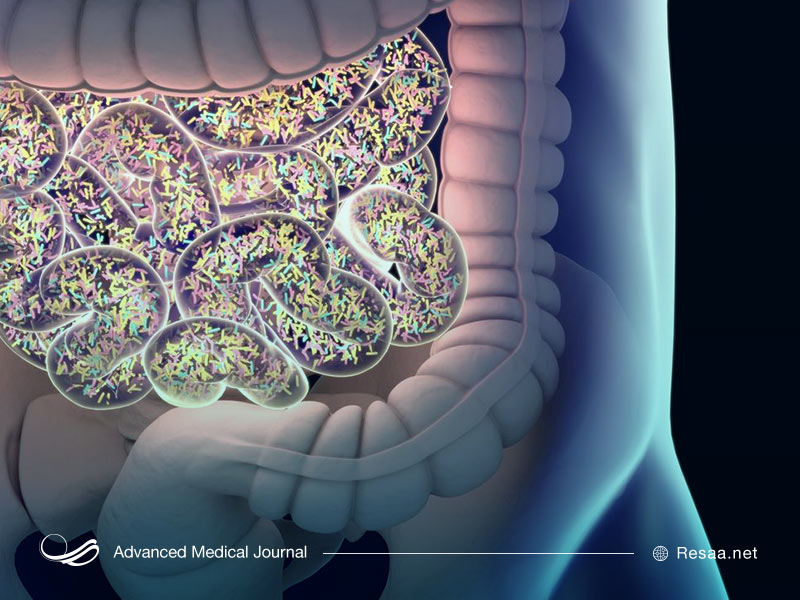

- التهاب روده

- غذاهای حاوی باکتریهای فعال مانند ماست